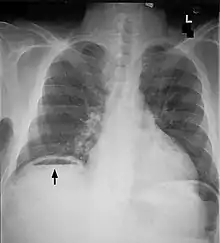

| Frontal chest X-ray. The air bubble below the right hemidiaphragm (on the left of the image) is a pneumoperitoneum. | |